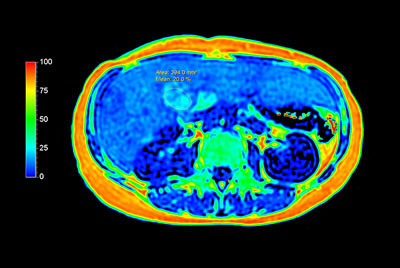

Liver quantification

mDIXON Quant - Steatosis

Advanced Liver MR - mDIXON Quant